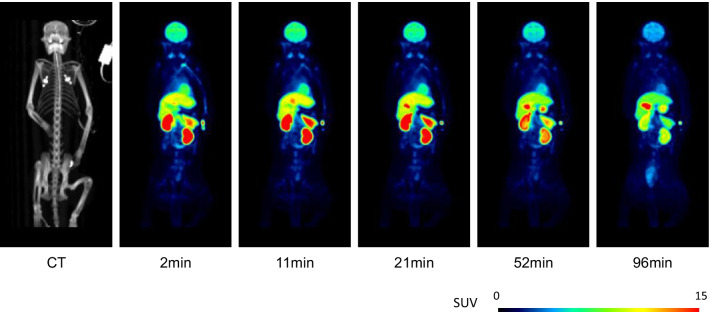

Whole body PET

The injected radioactivity of [11C]PF-06809247 was 272 and 302 MBq for the two measurements, respectively. The molar radioactivity at the time of injection was 186 and 494 GBq/µmol, and the injected mass was 0.6 and 0.3 µg for the two measurements, respectively. High uptakes were observed in the liver, small intestine, kidney, and brain (Figs. 6, 7a, b). The effective dose is 4.3 μSv/MBq (Table 3).

The whole-body measurement showed highest accumulation in the liver and small intestine, and relatively low accumulation in the urinary bladder. Notably, the uptake in the brain was also high (7% ID at peak). The effective dose of [11C]PF-06809247 was 4.3 μSv/MBq, which was similar to the median value (4.7 μSv/MBq) of other carbon-11 PET radioligands [ref. 18]. This radiation exposure would allow multiple administrations in a single subject enabling longitudinal and/or baseline blocking studies in human.